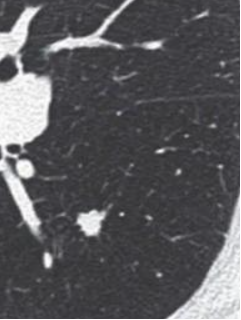

肺结节的密度根据其是否掩盖其中走形的血管和支气管分为实性结节、纯磨玻璃结节、混合磨玻璃结节(指其内既有纯磨玻璃密度、又有实性部分)。下面通过图片来展示。

实性结节